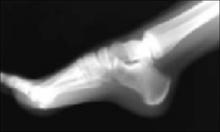

Is this x-ray normal? You order a lateral x-ray of the calcaneus to exclude other pathology. You observe a pattern of increased density and apparent irregular fragmentation on the x-ray. The radiologist reports no abnormal findings. The above x-ray typifies calcaneal apophysitis, an overuse syndrome often seen in children 8 to 15 years of age. The “dense” area is actually a secondary ossification center of the calcaneus, not an indication of pathology.